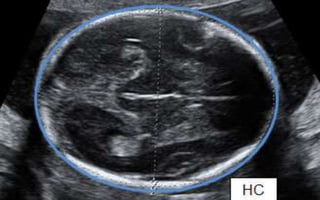

Head Circumference (HC)

• An essential parameter for the estimation of fetal weight as

well as in cases with abnormal fetal head size (i.e.,

microcephaly/macrocephaly)

Occipito-frontal Diameter (OFD)

• Distance between the back of the head and the forehead.

• To assess the growth and development.

• an important indicator of overall fetal health and well-being.